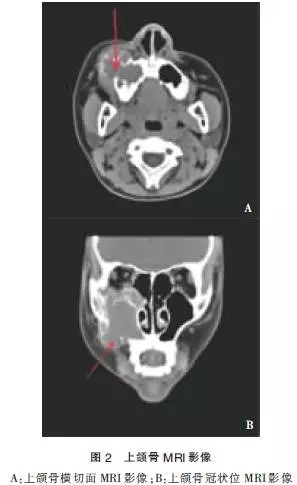

患者于2014-03-14行MRI檢查示:右側(cè)上頜竇為中心,右側(cè)眶下壁至上頜骨區(qū)頜面部可見(jiàn)一不規(guī)則形軟組織信號(hào)腫塊影,大小約4.2 cm×4.7cm×5.9cm。輪廓不光整,病灶可見(jiàn)斑點(diǎn)狀,棒狀短T1高信號(hào),短T2低信號(hào)影,輪廓清晰。病灶部分突入右側(cè)鼻腔內(nèi),鼻中隔居中,注射造影劑后上述病灶呈不均勻顯著異常強(qiáng)化,右側(cè)額竇、篩竇及蝶竇內(nèi)可見(jiàn)長(zhǎng)T2高信號(hào)影。

影像學(xué)診斷:①右側(cè)頜面部占位,血管瘤或惡性腫瘤可能;②垂體形態(tài)不規(guī)則,請(qǐng)結(jié)合臨床考慮(圖2)。于2014-03-18行“頸內(nèi)外動(dòng)脈造影+血管瘤供血?jiǎng)用}栓塞術(shù)”,患者仰臥,心電監(jiān)護(hù)下,常規(guī)右腹股溝消毒,鋪無(wú)菌巾,2%利多卡因局麻后,以技術(shù)穿刺右股動(dòng)脈,置入5F鞘管送5F單彎導(dǎo)管分別選擇性進(jìn)入兩側(cè)頸動(dòng)脈。右側(cè)頸內(nèi)外動(dòng)脈造影(圖3):右側(cè)頜面部可見(jiàn)富血供染色病灶,呈現(xiàn)“血管湖”徑,右側(cè)頜內(nèi)動(dòng)脈為主要供血?jiǎng)用},參與約80%供血,右側(cè)面動(dòng)脈及顳淺動(dòng)脈分支參與約10%供血,右側(cè)眼動(dòng)脈分支參與約10%供血,左側(cè)頸內(nèi)動(dòng)脈及各大腦動(dòng)脈及其分支顯影清晰,未見(jiàn)明顯異常。

MRI表現(xiàn)為骨髓腔內(nèi)不均勻的信號(hào)強(qiáng)度,T1T2加極像呈低信號(hào)影。如果伴發(fā)周圍軟組織的高流速血管畸形,則在MRI上顯示為不規(guī)則的蜂窩狀流空血管巢及不規(guī)則曲張異常的流空血管影,注射增強(qiáng)劑后未見(jiàn)明顯強(qiáng)化。